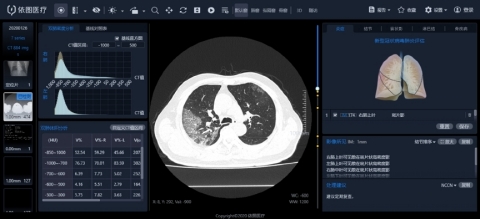

BEIJING--(BUSINESS WIRE)--Op 4 februari publiceerde het Shanghai Public Health Clinical Center, een van de toonaangevende instellingen op het gebied van infectieziekten in China en de kerneenheid voor de behandeling van COVID-19 in Shanghai, het artikel “AI Aids het Wetenschappelijke Preventie en Controle, Intelligente Evaluatiesysteem van CT van de borst voor COVID-19 gelanceerd in het Shanghai Public Health Clinical Center ”op zijn officiële WeChat-platform.

Het artikel kondigde de nieuwste resultaten aan van het gebruik van kunstmatige intelligentietechnologie om artsen te helpen bij het uitvoeren van intelligente kwantitatieve analyse en evaluatie van therapeutische effecten van nieuwe coronaviruslaesies op basis van CT-beelden.